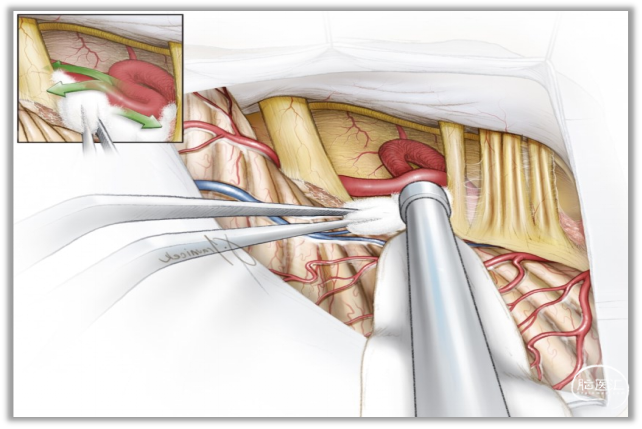

小脑绒球下入路(infrafloccular approach)最早由日本专家Matsushima提出。因为绒球和从Luschka孔突出的脉络丛从外侧遮挡面神经REZ区(下图),而且,在绒球和前庭蜗神经之间经常有黏连,还可能存在大量坚韧的蛛网膜小梁,因此从小脑外侧间隙很难暴露REZ区,还可能造成听力损伤。

此时重要的是要牢记面神经出脑干处位于舌咽神经入脑干处上方2~3mm。

绒球下入路(上图)就是抬起小脑的下外侧缘,打开舌咽神经和迷走神经后方的蛛网膜,便可暴露由Luschka孔突出的位于舌咽神经和迷走神经后面的脉络丛,将脉络丛从舌咽神经后缘轻轻分开,以暴露舌咽神经与脑干连接处。脑板进一步向上将脉络丛从舌咽神经后缘上抬起,暴露范围向舌咽神经上方扩展数毫米,此处即为面神经与脑干的连接处(REZ区),恰位于前庭蜗神经的前下方。

可以采用聚四氟乙烯(Teflon)单点支撑(下图)、桥型支撑、棉条悬吊、胶水黏附悬吊等。责任血管(一般是小脑前下或后下动脉)就在面神经的腋部,抬起血管,将血管与神经分离后即可垫入Teflon。

减压垫棉置于责任血管与脑干之间,必要时可用第2、第3 块垫棉进一步推开血管以求减压充分。有学者建议应避免将垫棉放置在责任血管与面神经出脑干区之间,亦不可与之接触以防局部发生粘连而致术后复发(桥型支撑)。另有学者建议责任血管与面神经REZ区域及脑干相邻全程均要用Teflon垫开(下图)。